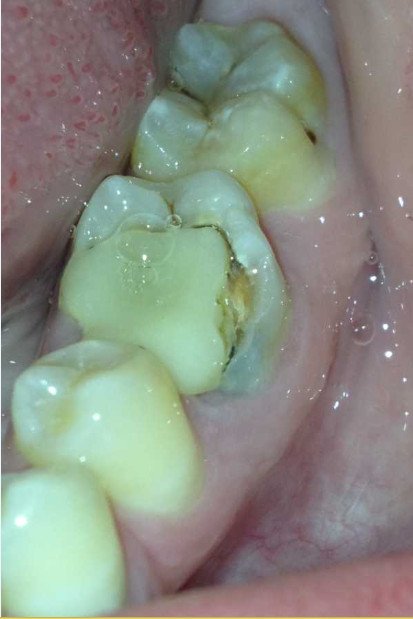

Сломала пол переднего резца. Поставили световую пломбу, была довольна. Со временем зуб потемнел, и граница пломбы стала видна, да и сама пломба сточилась немного. Можно ли ее заменить под более подходящий цвет зуба?

Добрый день. Да, конечно можно, но я вам рекомендую изготовить терапевтический винир, то есть необходимо перекрыть всю фронтальную часть зуба, чтобы избежать трещин пломбы на границах с зубом либо установить коронку.

Оба метода актуальны и правильны, все зависит от ситуации и объема оставшихся тканей зуба!